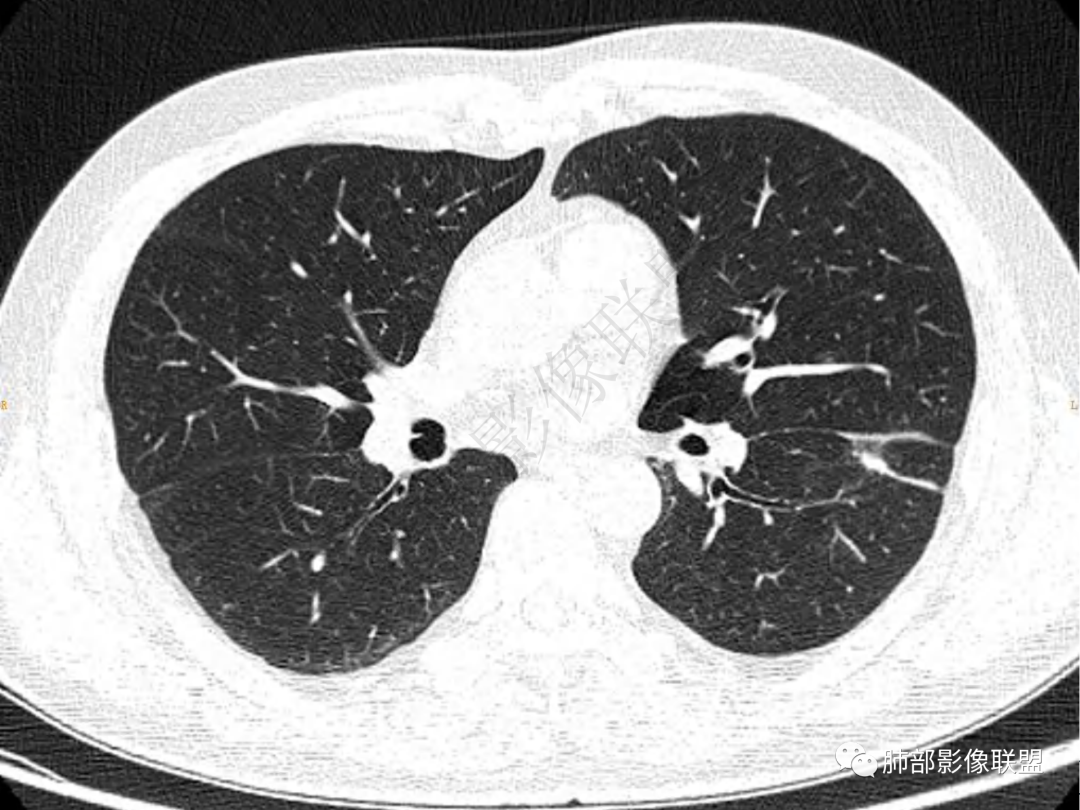

2.左肺下叶团片影,跨背段及内前基底段,实性部分类椭圆形,密度不甚均匀,可见毛刺及棘状突起,未见典型分叶及胸膜凹陷。病灶上下缘可见相应肺段支气管旁进侧出,管壁轻度增厚,未见狭窄阻塞。

3.周边较大范围磨玻璃影,边界相当模糊,小叶增厚明显。注意叶裂另一侧、左肺舌段亦可见磨玻璃影及增厚的小叶间隔。未见明确卫星病灶。

1.病灶不够密实,没有典型分叶,收缩乏力等,支气管未见截断等,缺乏一般肿瘤性肿块特征。

2.周围磨玻璃影边界不清缺乏限制,甚至“激惹”到相邻肺叶,也许提示较明显的炎性水肿。

正如多数老师分析到的,本例病灶炎性特点比较明显。